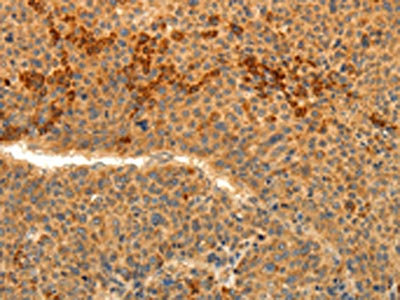

The image on the left is immunohistochemistry of paraffin-embedded Human colon cancer tissue using CSB-PA032588(TRPM7 Antibody) at dilution 1/30, on the right is treated with synthetic peptide. (Original magnification: ×200)

The image on the left is immunohistochemistry of paraffin-embedded Human liver cancer tissue using CSB-PA032588(TRPM7 Antibody) at dilution 1/30, on the right is treated with synthetic peptide. (Original magnification: ×200)